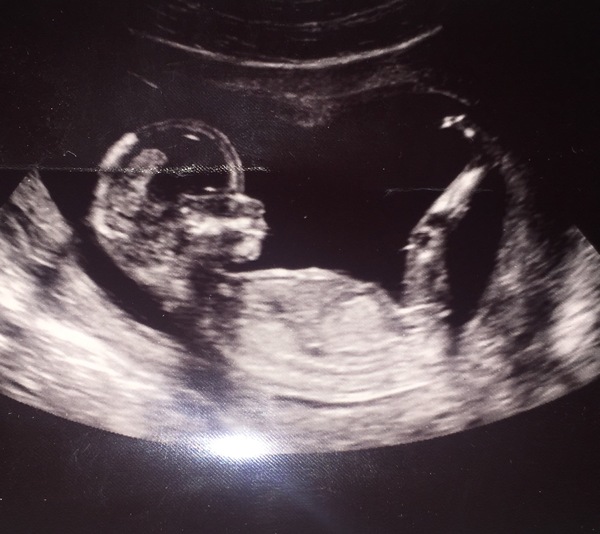

Wow have just caught up, congratulations everyone on your healthy scans! I was so scared about mine, I was distraught today going in, but all was fine and we got to watch baby for about an hour because we had a trainee sonographer and baby wasn't playing ball so I had to keep jumping around, being tipped up, rocked side to side, coughing etc! Until they could take all the measurements. Measuring bang on what we thought, 14 weeks today, and they gave us 6 pics for free instead of the standard 3 that we are meant to pay for because I was such a snivelling mess lol. So happy. We got a freaky X Files style hand pic too!

Hazandduck · 15/05/2017 21:23

This is the scan, baby has NOT got my stumpy little legs, lucky bugger :)

@Hazandduck you have such beautiful scan photos!

Amazing photos haz! It's like the baby is saying 'oi, stop prodding!'Grin

Thank you Mrs I can't stop staring at them, it kind of weirds me out to think of these tiny hands inside me! Haha it really was saying "talk to the hand!" X

Lovely scan Haz x

@Hazandduck what a brilliant picture.